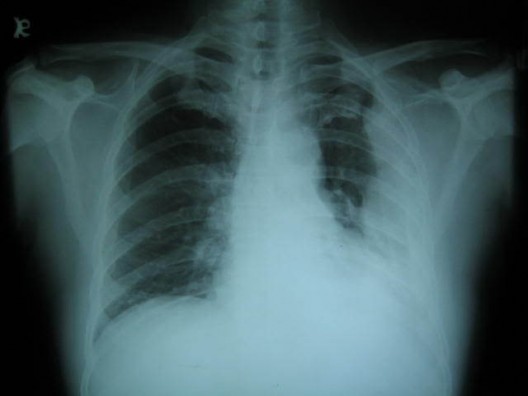

Image info: Mesothelioma XRay Findings : 528 x 396 shared from https://blogger.googleusercontent.com/img/b/R29vZ2xl/AVvXsEhO1BXorQJ-LHpJYC5uLM9zAKAvhYZXZJhRRDjFkxSxJsr5C_JvW-Q6Jmg8iUI-CzpnBOUSXUGFOzL0jLF9jbBEIGKdIfHZ8-TMwD6IKP3agxRHLCB3jMoKxKUYiSll7J9Od8TjXtDMeJI/s1600/Colorado_mesothelioma-lawyers.jpg